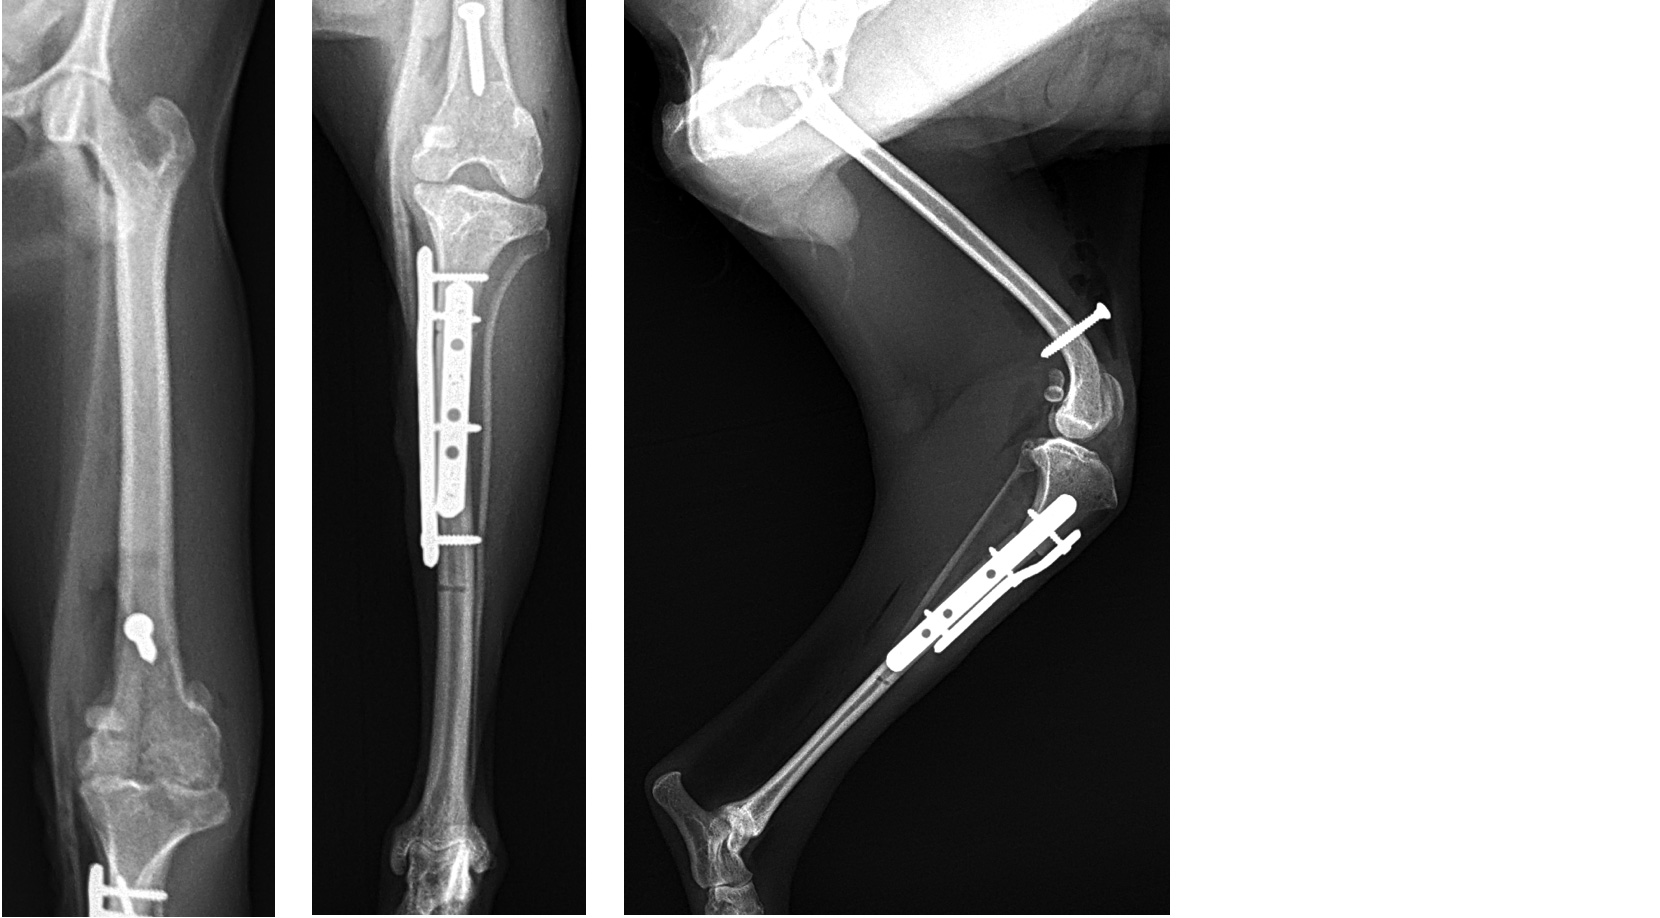

当院では、こうした症例に対して以下のような手術手技を症例ごとに適切に組み合わせ、「歩けるようになること」、「痛みなく生活できること」を目指しています。

骨の変形が疑われる場合には、以下のような段階を踏んで安全かつ精度の高い手術を行います。

※骨変形が高度な場合、滑車溝形成術と矯正骨切り術を分割して実施することで、安全性と整復精度を確保します。